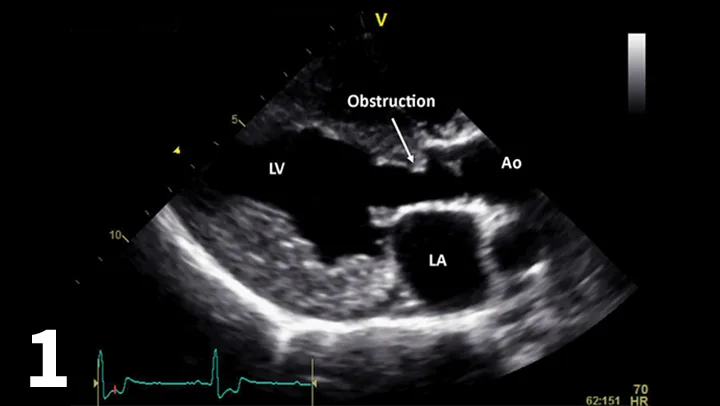

Figure 1.

Right-sided 5-chamber long-axis view showing the left ventricular (LV) outflow tract. The LV is hypertrophied, and there is an obstructive ridge in the LV tract below the valve. (Ao = aorta; LA = left atrium)